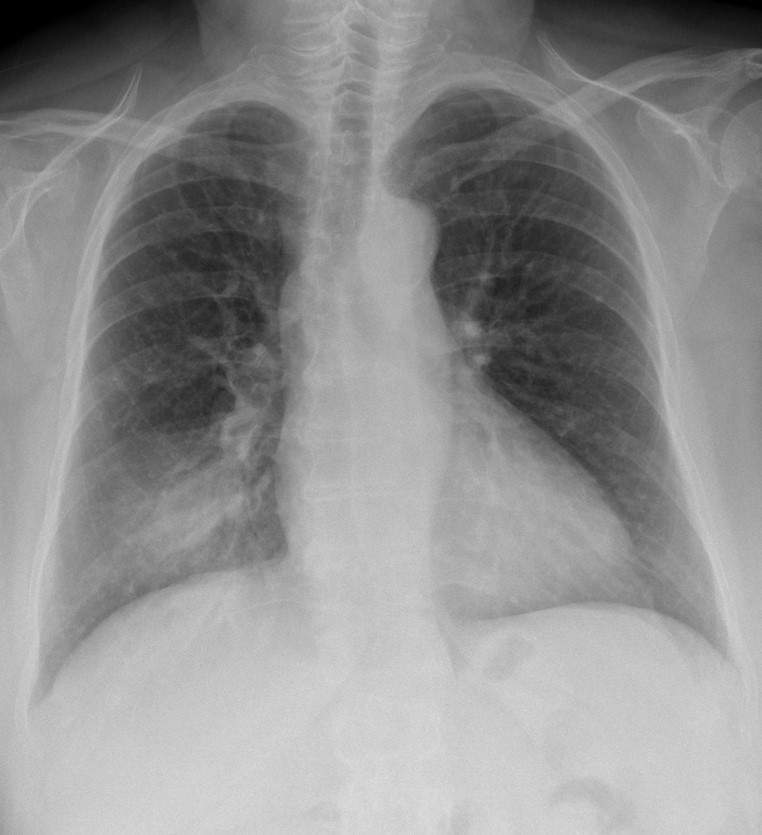

What is the most accurate description of this chest x-ray?

a) Right lower lobe pneumonia

b) Congestive heart failure

c) Covid pneumonitis

d) Left pneumothorax

e) Normal chest x-ray

A